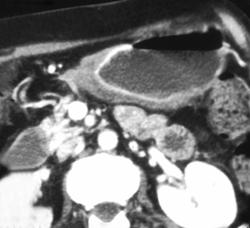

Gastric Ulcer